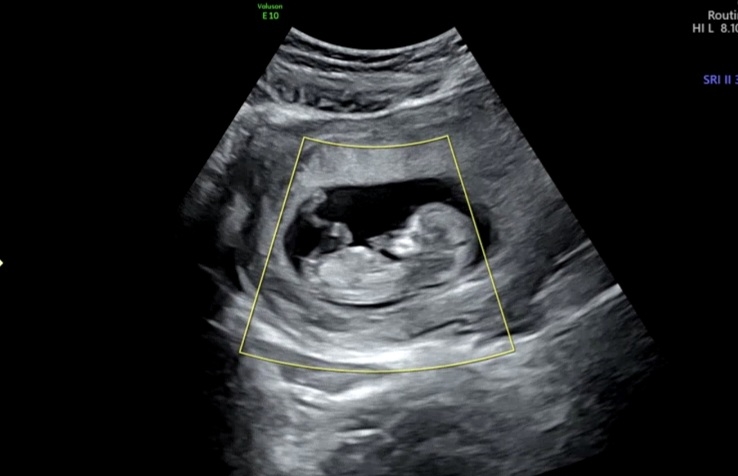

각도법 한번 봐주세요 🙏

11주5일차 초음파사진이에요 !! 아들일까요? 딸일까요?